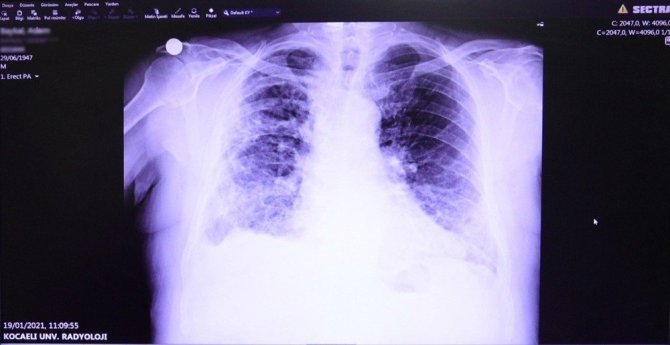

Kocaeli Üniversitesi Tıp Fakültesi Göğüs Hastalıkları Ana Bilim Dalı Öğretim Üyesi Prof. Dr. İlknur Başyiğit, Covid-19 salgını sebebiyle merak edilen soruları Kocaeli Büyükşehir Belediyesi için cevapladı. Sağlık ve Sosyal Hizmetler Dairesi Başkanlığına açıklamada bulunan Prof. Dr. Başyiğit, hastalığın belirtileri, tedavi ve tedavi sonrasındaki süreci değerlendirdi.

Tedavi sürecinin hastalık için önemli olduğuna dikkat çeken Prof. Başyiğit, "Bu hastalıkta doktorun verdiği tedavi yönetimine kesinlikle uyulması gerekiyor. Pozitif olan hasta ile aynı evde bulunanlar kendilerini izole etmeleri gerekiyor. Tedavi süresince pozitif olan hasta veya yakınlarında oluşabilecek şiddetli nefes darlığı, öksürük, göğüs ağrısı gibi şikayetlerde de bir an evvel doktora başvurulması gerekiyor" diye konuştu.